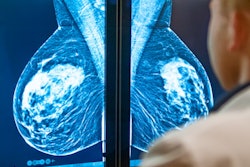

It's no secret that radiologists' interpretive accuracy on screening mammography can vary widely. But the particular factors that influence performance may come as a surprise, according to a study published June 22 in Radiology.

A team led by Dr. Cindy Lee of NYU Langone Health in New York City found that characteristics beyond a radiologist's time in practice, for example, can affect mammography interpretation performance.

"The geographic location of the radiology practice, subspecialization in breast imaging, and performance of diagnostic mammography are associated with better screening mammography [interpretations]," the authors wrote.